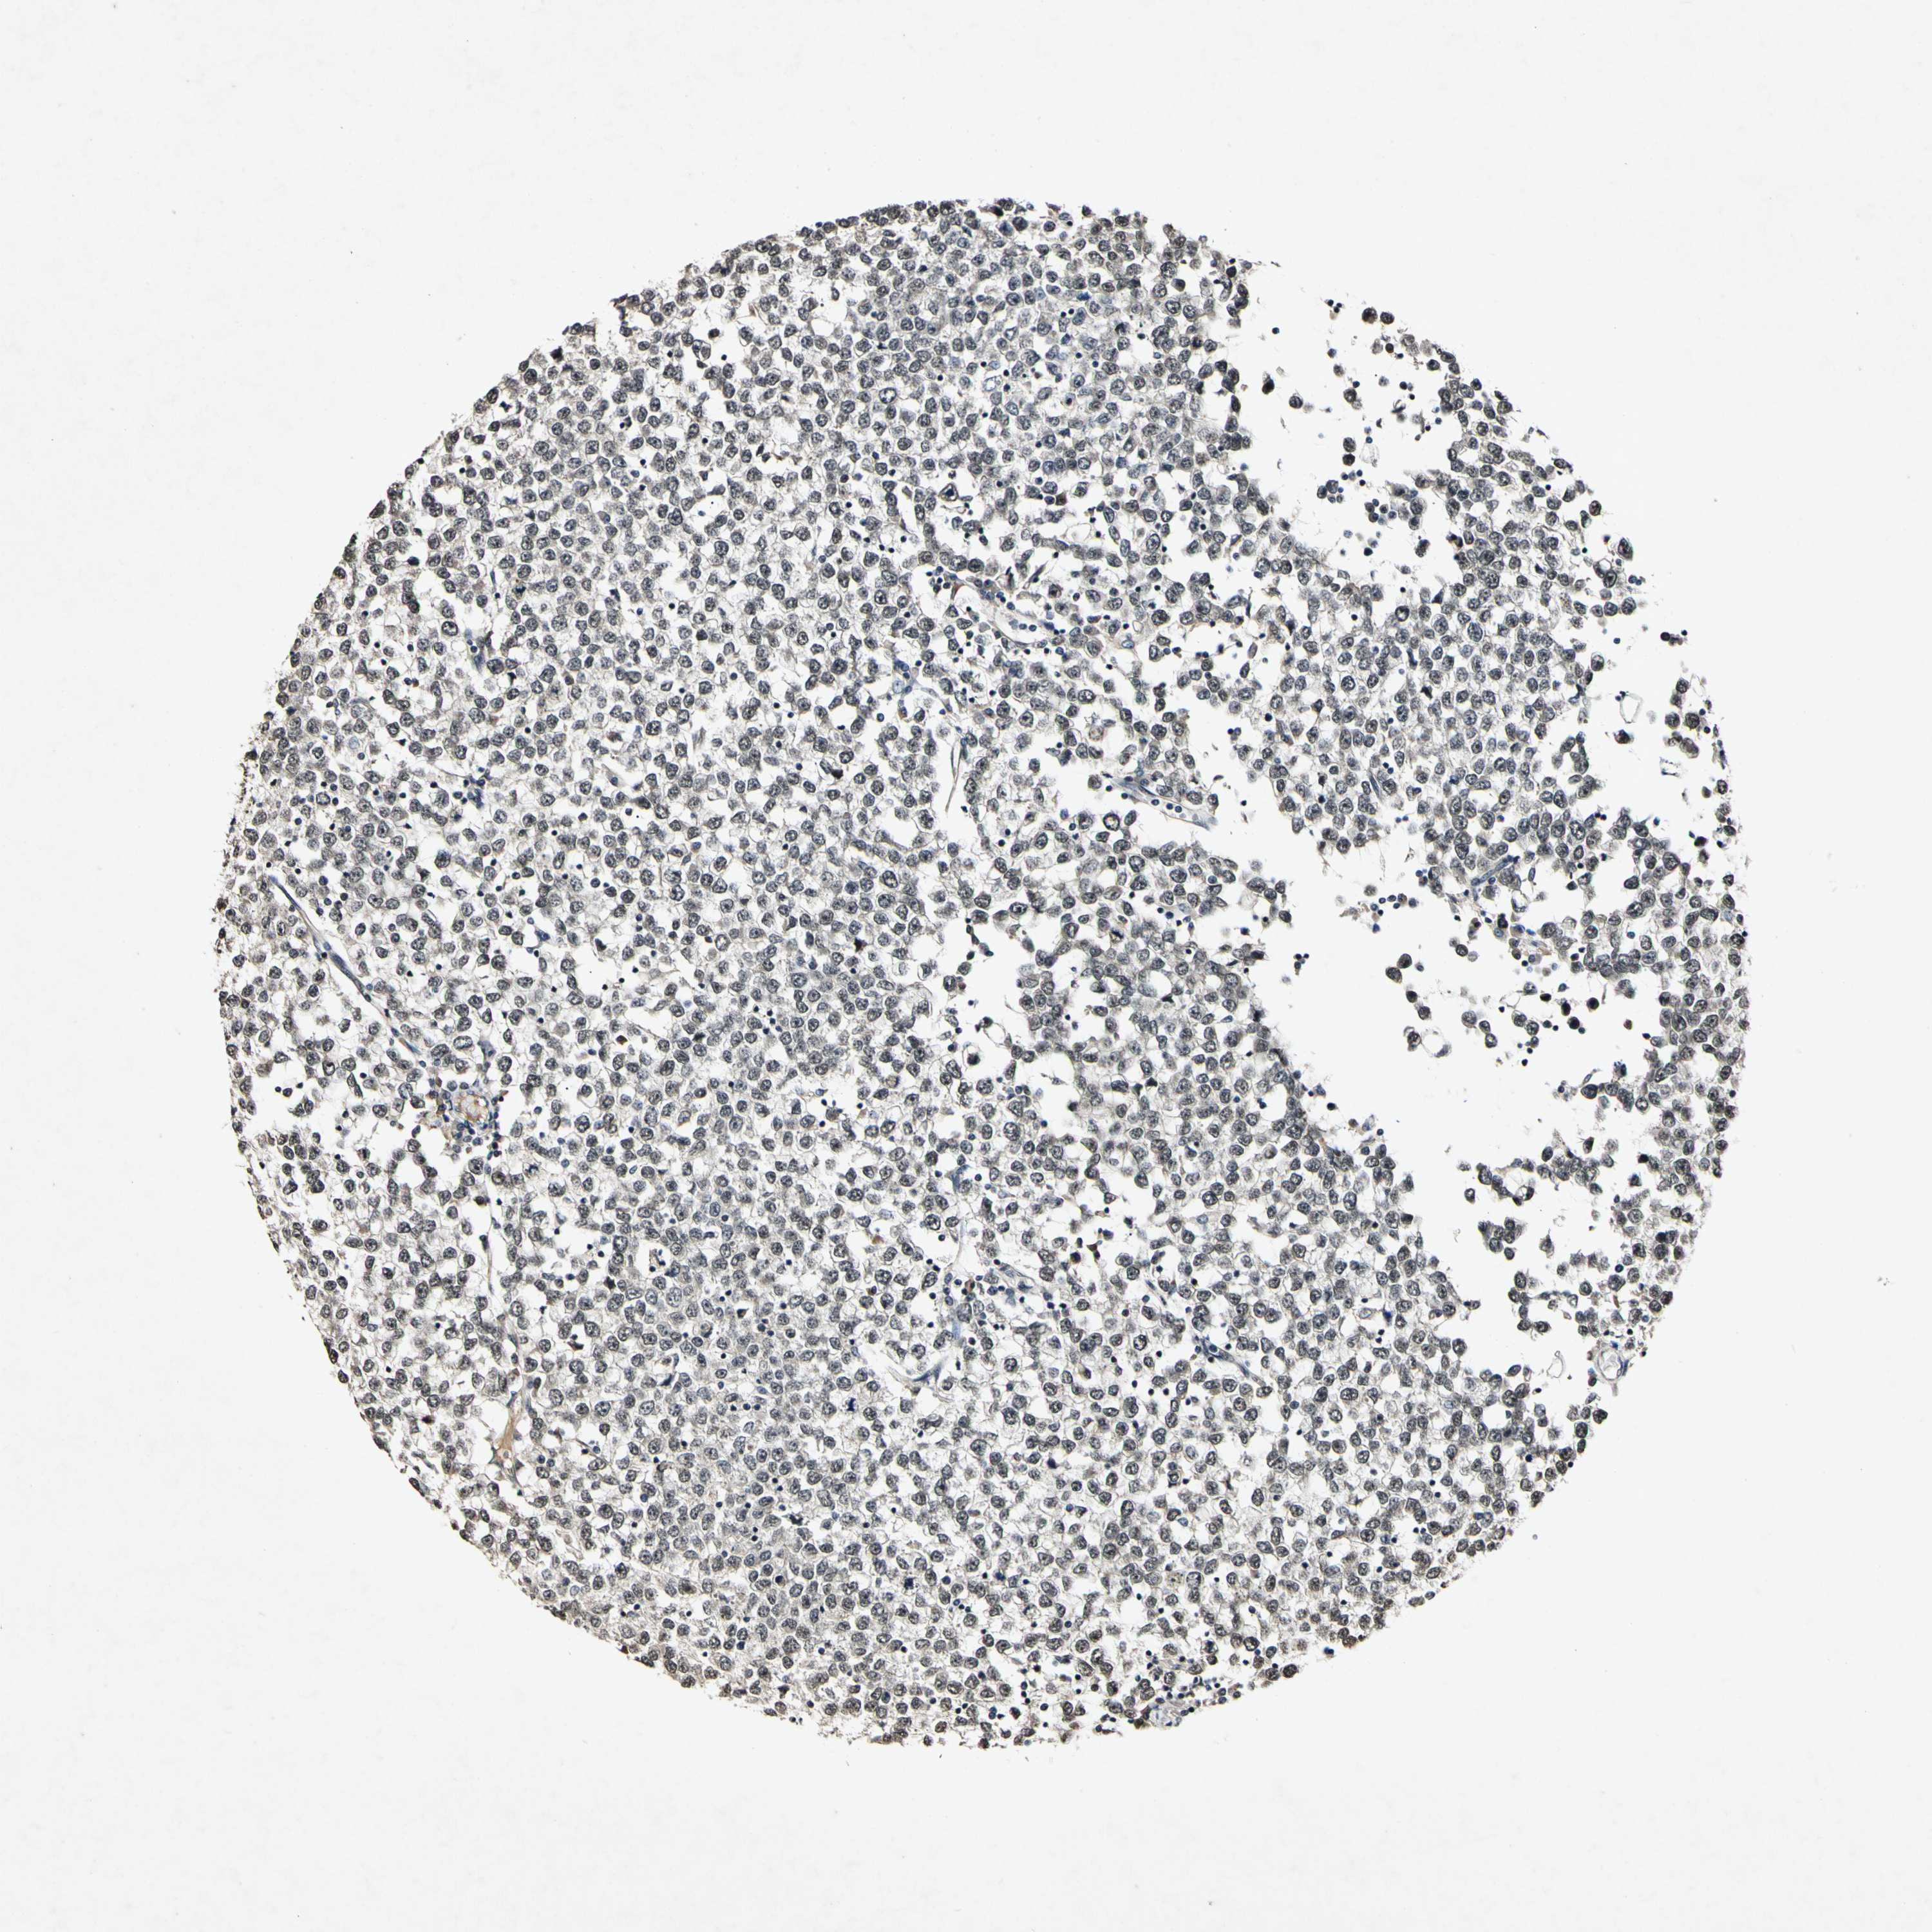

TESTIS CANCER - Protein expressioni

A mouse-over function shows sample information and annotation data. Click on an image to view it in a full screen mode. Samples can be filtered based on level of antibody staining by selecting one or several of the following categories: high, medium, low and not detected. The assay and annotation is described here.

Note that samples used for immunohistochemistry by the Human Protein Atlas do not correspond to samples in the TCGA dataset.

Antibody stainingi

Antibody staining in the annotated cell types in the current human tissue is reported as not detected, low, medium, or high, based on conventional immunohistochemistry profiling in selected tissues. This score is based on the combination of the staining intensity and fraction of stained cells.

Each image is clickable and will lead to virtual microscopy that enables deeper exploration of all samples and also displays staining intensity scores, fraction scores and subcellular localization as well as patient and tissue information for each sample.

Antibody HPA000827

Seminoma, NOS